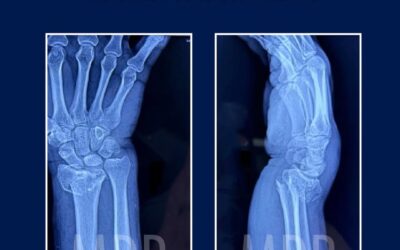

Fractura de Muñeca: Más común de lo que imaginas

En manos del Dr. Mario Dorantes Rodríguez, especialista en cirugía ortopédica, encontrarás tratamientos precisos y técnicas de fijación que restauran la función natural de tu muñeca.